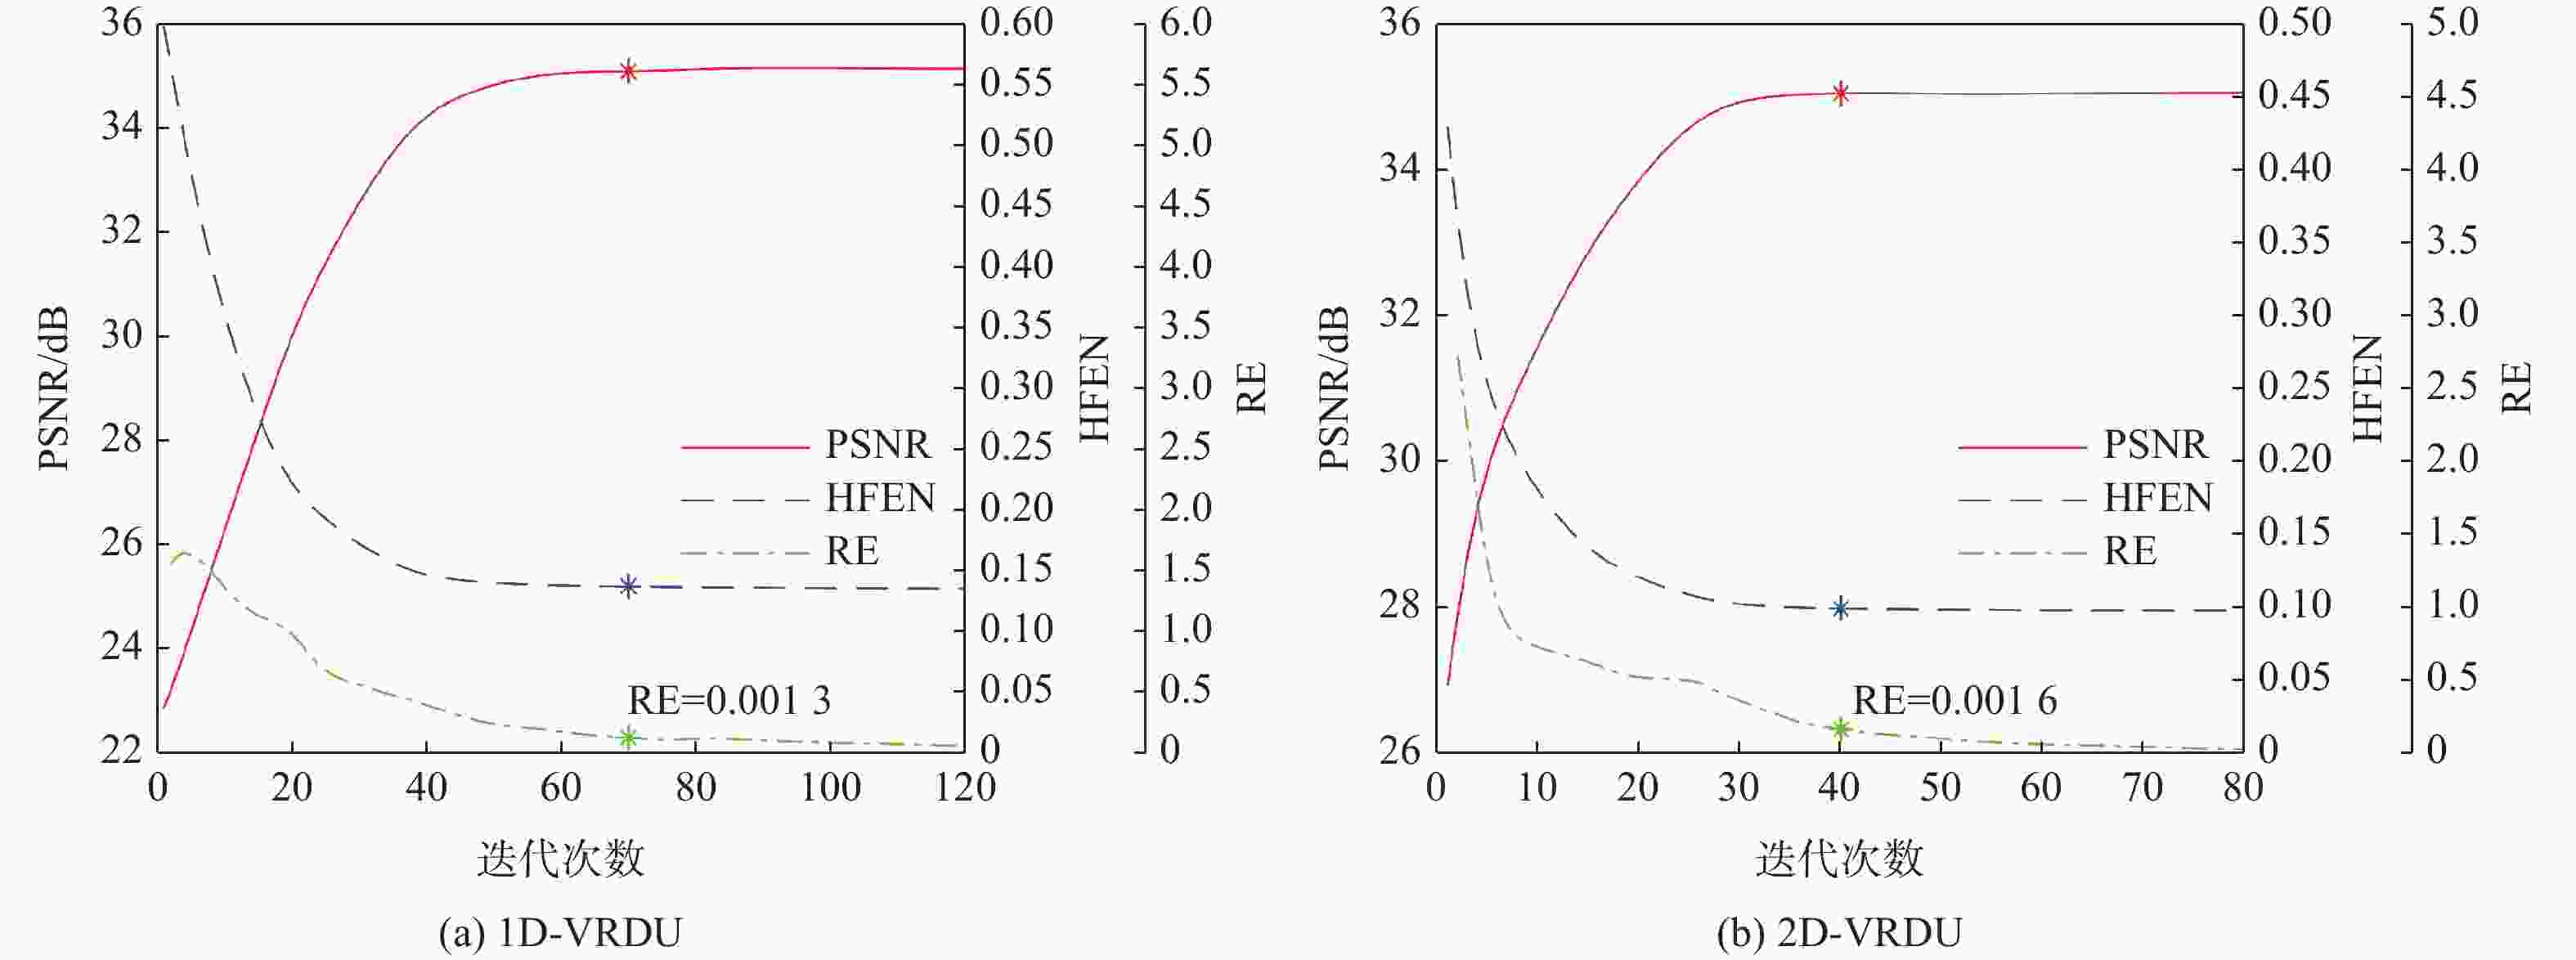

二维(2D)多切片磁共振数据在相邻切片之间具有高度的相关性,通过利用切片间的冗余性能够重建出更高质量的切片图像,但由于硬件条件的限制,2D多切片磁共振成像(MRI)需要耗费大量时间。为提高2D多切片磁共振图像的重建质量和重建速度,将联合稀疏变换学习正则项引入到多切片Hankel张量完成(MS-HTC)模型中,提出一种快速2D多切片磁共振成像重建(FMS-JTLHTC)算法。该算法使用交替方向乘子法对目标问题进行求解;引入快速迭代收缩阈值法加快收敛,并使用图形处理器对算法进行加速。使用4组脑部数据集在2种不同采样模式下进行实验,结果表明:FMS-JTLHTC算法的峰值信噪比(PSNR)相较于同时自动校准和K空间估计(SAKE)算法、并行成像数据的局部K空间领域的低秩建模(PLORAKS)算法和MS-HTC算法分别平均提高了4.04 dB、3.67 dB和2.07 dB,而且重建速度相比MS-HTC算法提高了14倍。

Abstract:Due to the significant correlation between neighboring slices in two-dimensional (2D) multi-slice magnetic resonance data, higher quality slice pictures can be reconstructed by taking use of the redundancy between slices. However, 2D multi-slice magnetic resonance imaging requires an amount of time. To improve the reconstruction quality and speed of 2D multi-slice (MRI) images, proposes a fast 2D multi-slice MRI reconstruction (FMS-JTLHTC) algorithm, which introduces the joint transform learning regular term into the multi-slice hankel tensor completion (MS-HTC) model. Prior to introducing the fast iterative shrinkage-thresholding procedure to accelerate convergence and utilize the graphics processing unit to speed up the procedure, the alternating direction method of multipliers is used to solve the objective issue. Experiments using four brain datasets in two different sampling modes show that the peak signal-to-noise ratio (PSNR) of the FMS-JTLHTC algorithm is improved by an average of 4.04 dB, 3.67 dB, and 2.07 dB compared to the simultaneous atuo-calibrating and K-space estimation (SAKE), low-rank modeling of local K-space neighborhoods with parallel imaging data (PLORAKS) and MS-HTC algorithms, respectively, the reconstruction speed is improved by a factor of 14 compared to the MS-HTC algorithm.